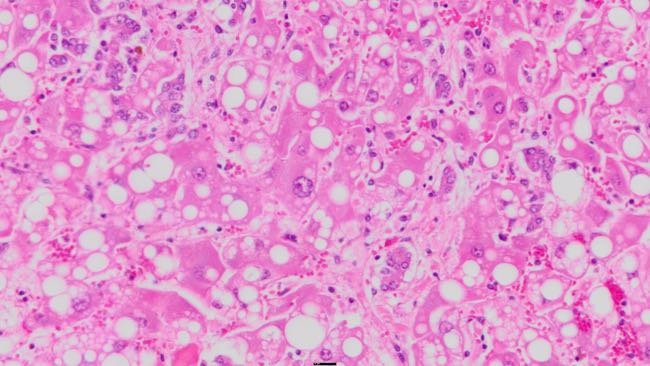

On histopathology of the liver there was severe diffuse fatty degeneration of hepatocytes, which was most prominent in periportal areas. Portal triads showed marked proliferation of bile ductules and mild fibrosis. Bile pigment was noted in canaliculi, hepatocytes and Kupffer cells. There was a marked variation in cellular and nuclear size of hepatocytes with presence of megalocytes and binucleated cells, and rare asymmetrical mitotic figures. Low numbers of neutrophils and lymphocytes were scattered in the parenchyma, with occasional clusters of neutrophils.

This cow had a severe subacute hepatopathy with severe fatty hepatocyte degeneration, megalocytosis, biliary proliferation, mild fibrosis, bile stasis and rare aberrant mitotic figures. These changes are consistent with a toxic hepatopathy, and considering the history and exposure to lupin stubbles it is highly likely that this cow had Phomopsin intoxication.